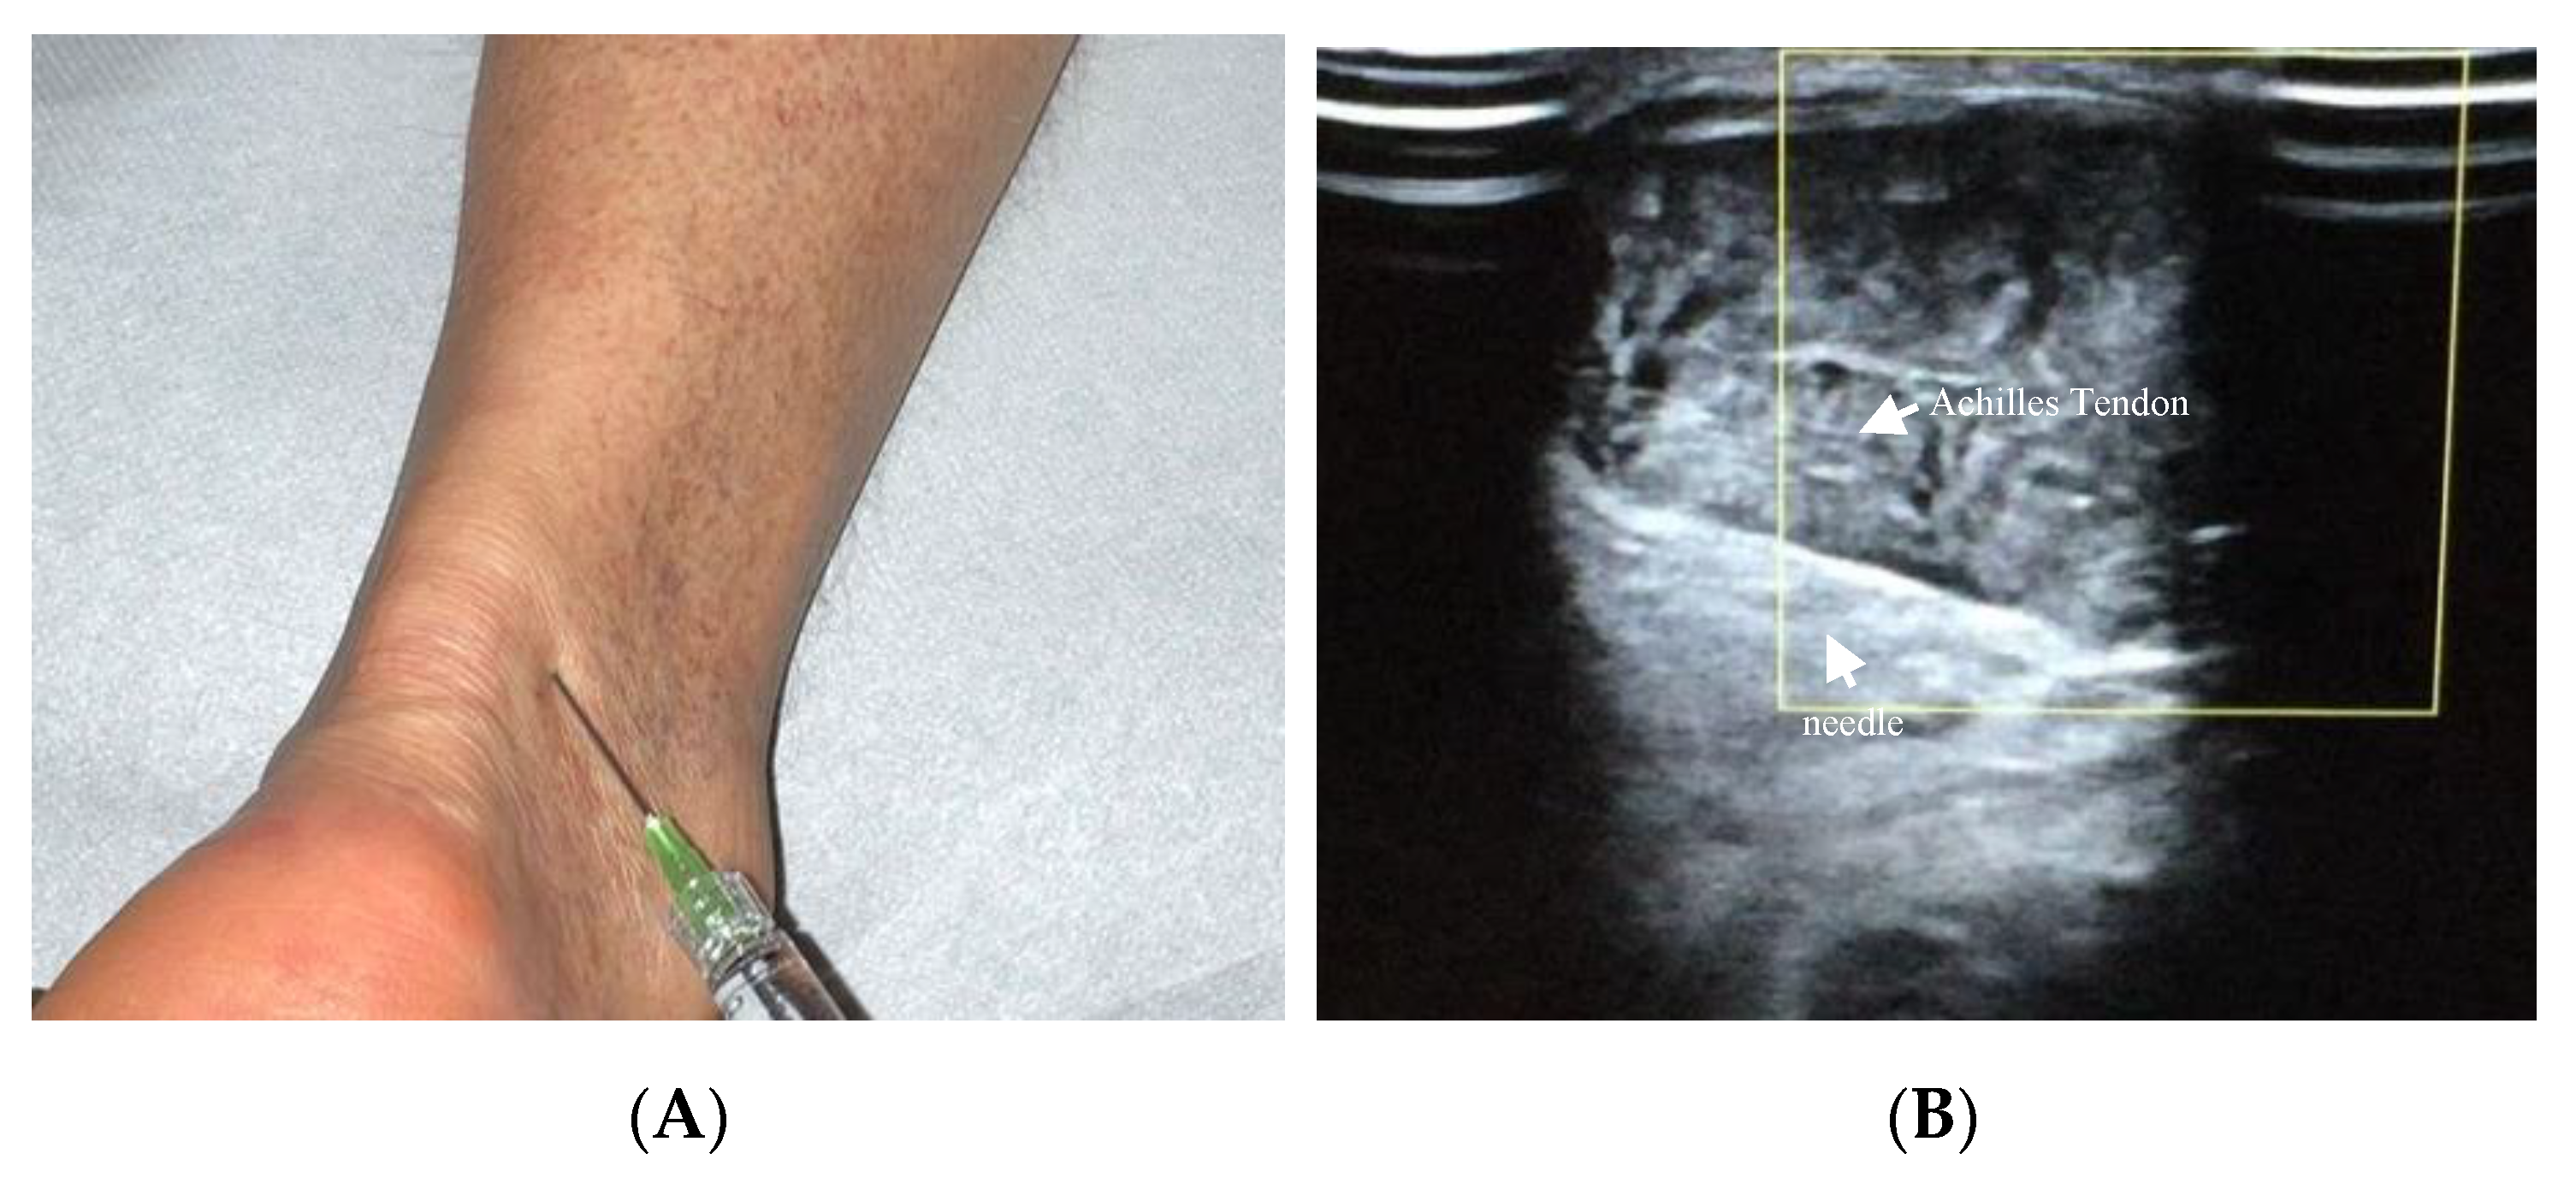

Achilles tendinopathy affects mainly athletes, especially runners, but also non-athletes [95]. The therapeutic use of HA in Achilles tendinopathy has been recently described (Figure 3A,B). Lynen et al. compared the effects of two HA peritendinous injections with shockwave therapy in patients with mid-portion Achilles tendinopathy. At 6 months, patients treated with HA injections reported better outcomes, with greater symptom improvement and restored function [14]. Similarly, Fogli et al. and Frizziero et al. showed that three US-guided medium molecular weight HA injections induce a clinically relevant increase in VISA-A values, pain relief, and US parameters improvement [10,93]. Recently, Gervasi et al. investigated the clinical, viscoelastometric, and biochemical effects of three US-guided medium molecular weight HA injections in runners with unilateral Achilles tendinopathy. Indeed, patients reported improvement in clinical assessment, decreased pain and stiffness of the tendon, and reduction in the viscoelastometric and functional asymmetry between the affected tendon and the healthy limb [96,97].

Figure 3.

(A) Injection of HA in a dorsolateral approach of Achilles tendon; (B) US visualisation (5–12 MHz linear probe and PRF set at 0.5 kHz) of the needle (22-gauge) introduced at a 30-degree angle in the mesotendon, with the probe in a transverse plane.